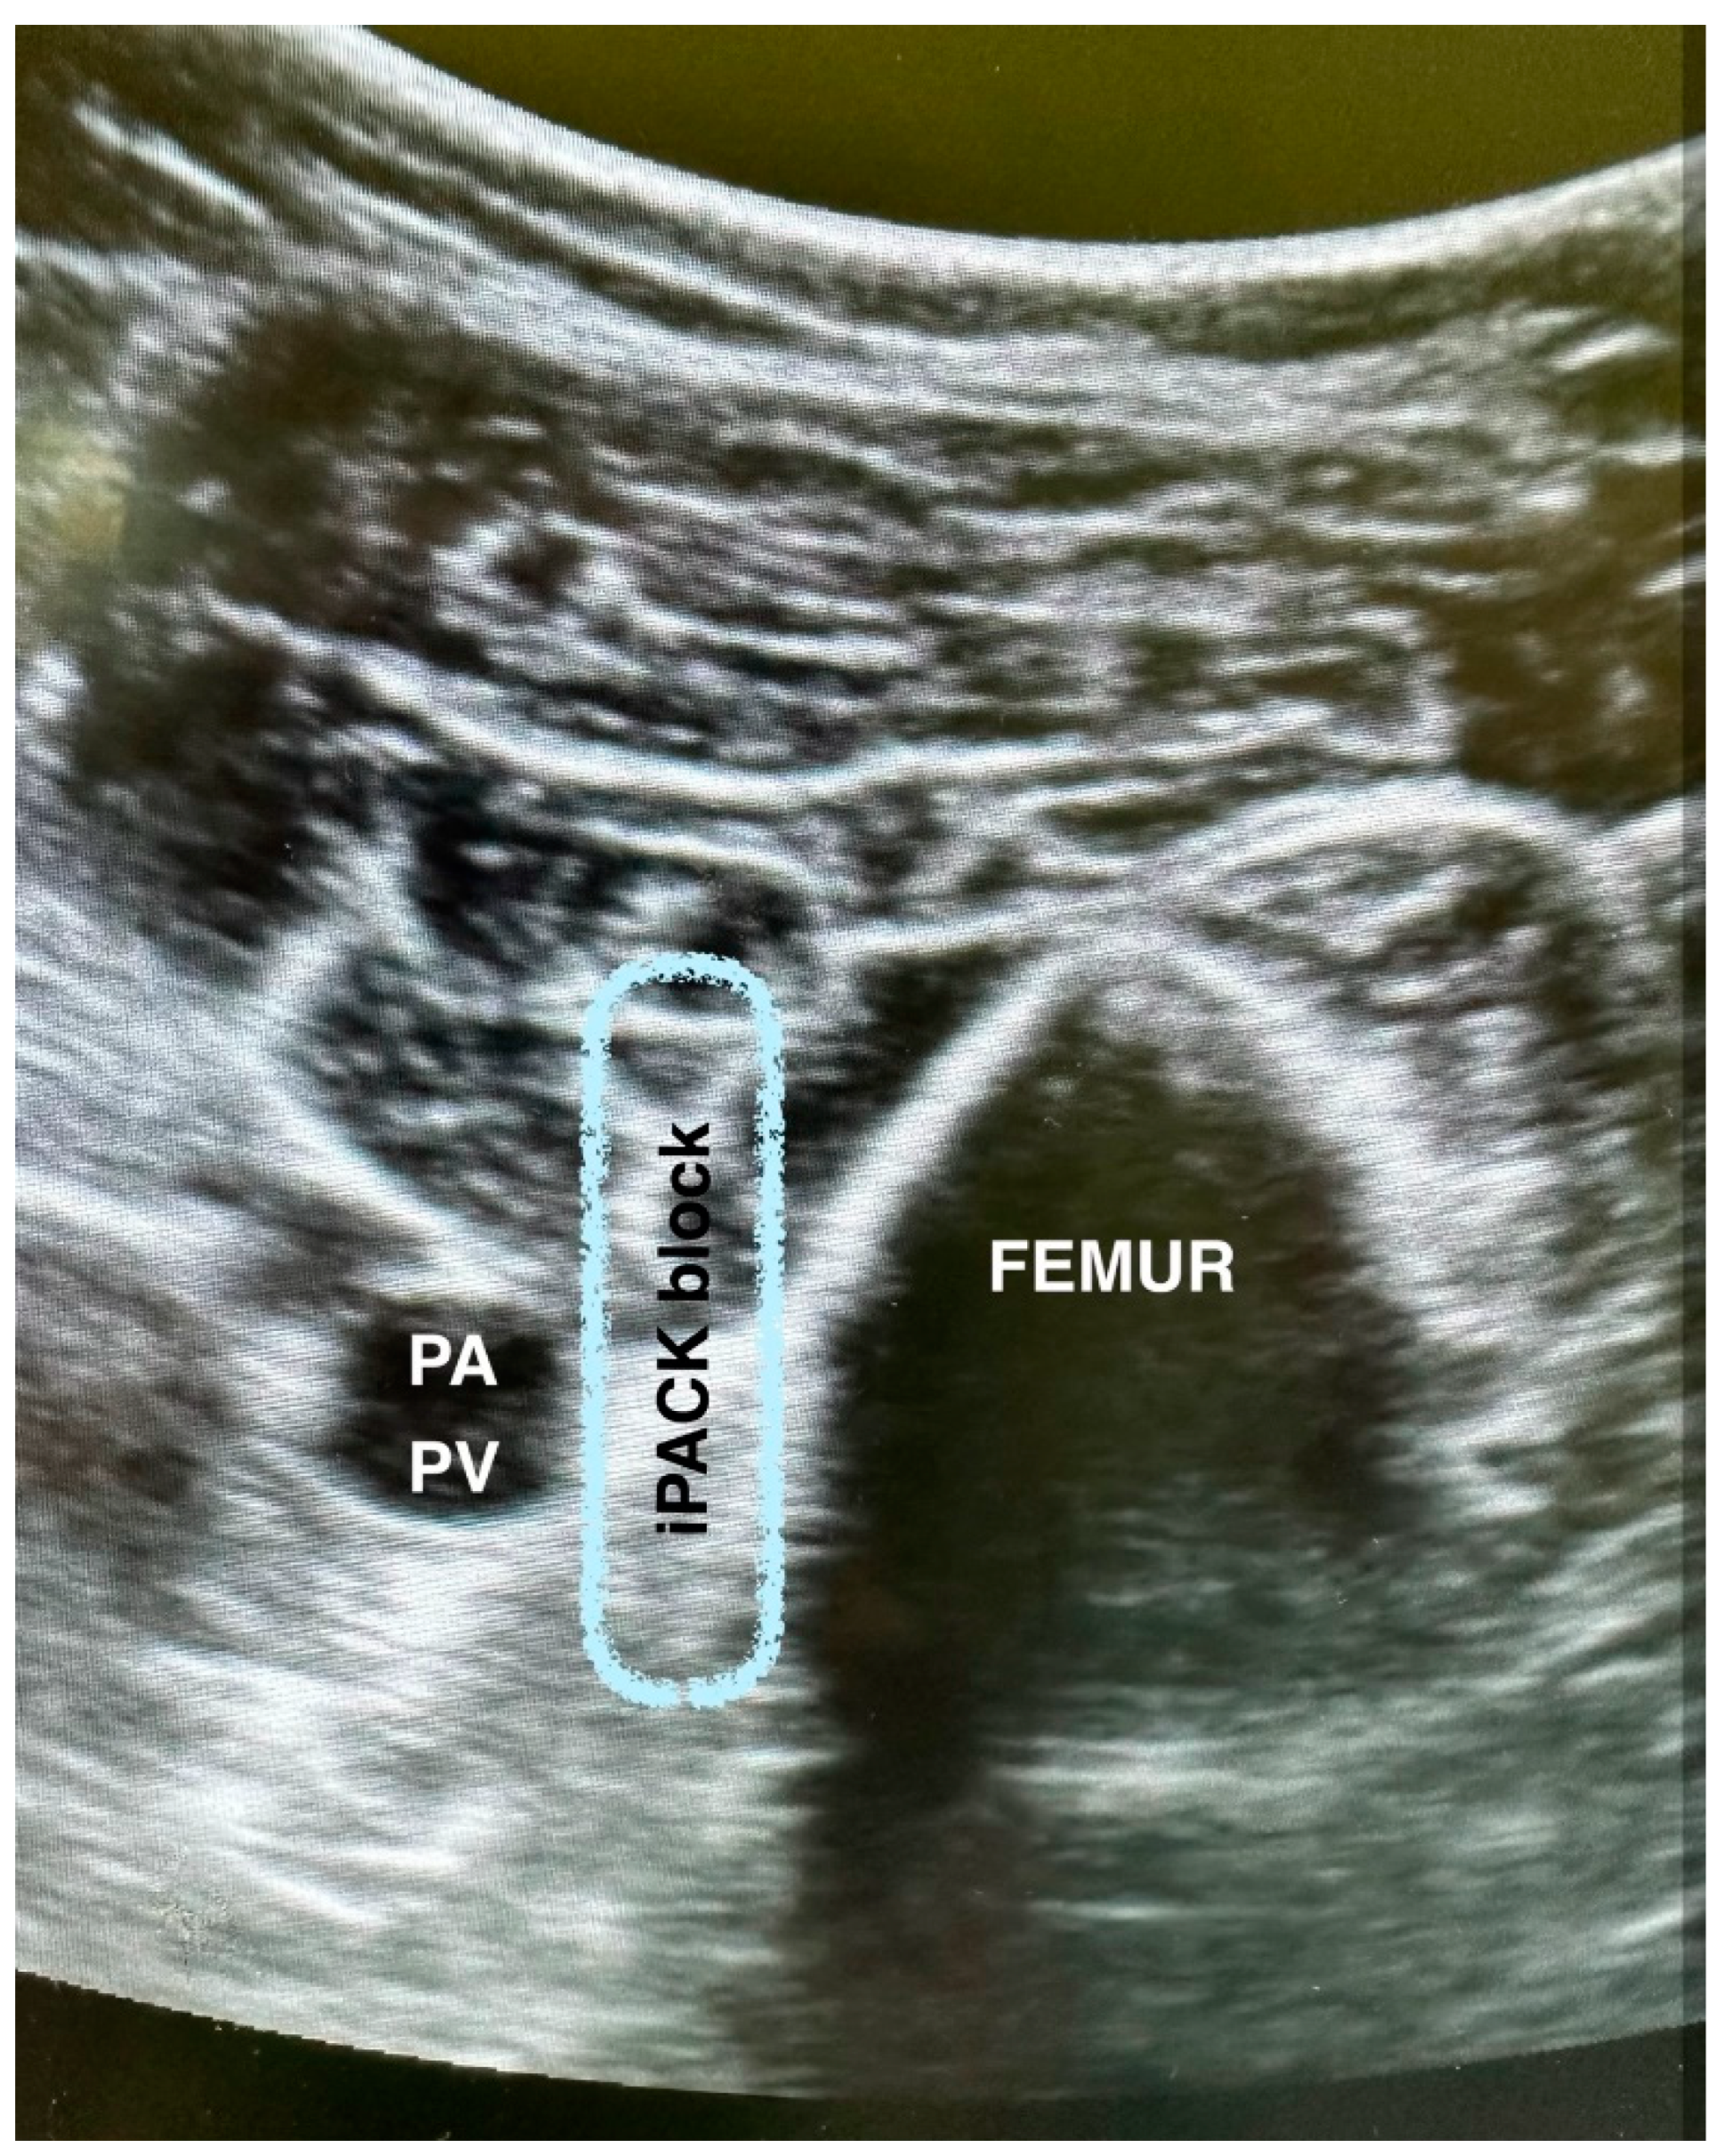

2.4. iPACK (Infiltration between the Popliteal Artery and the Capsule of the Posterior Knee) Block Procedure (Figure 1)